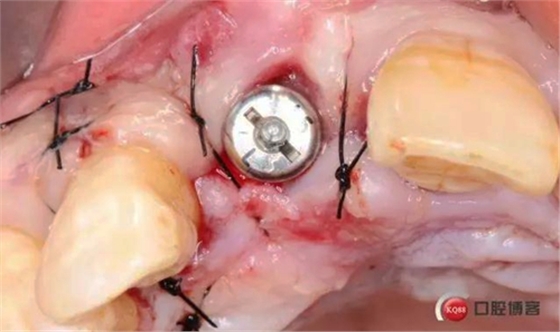

術前CBCT

術后縫合